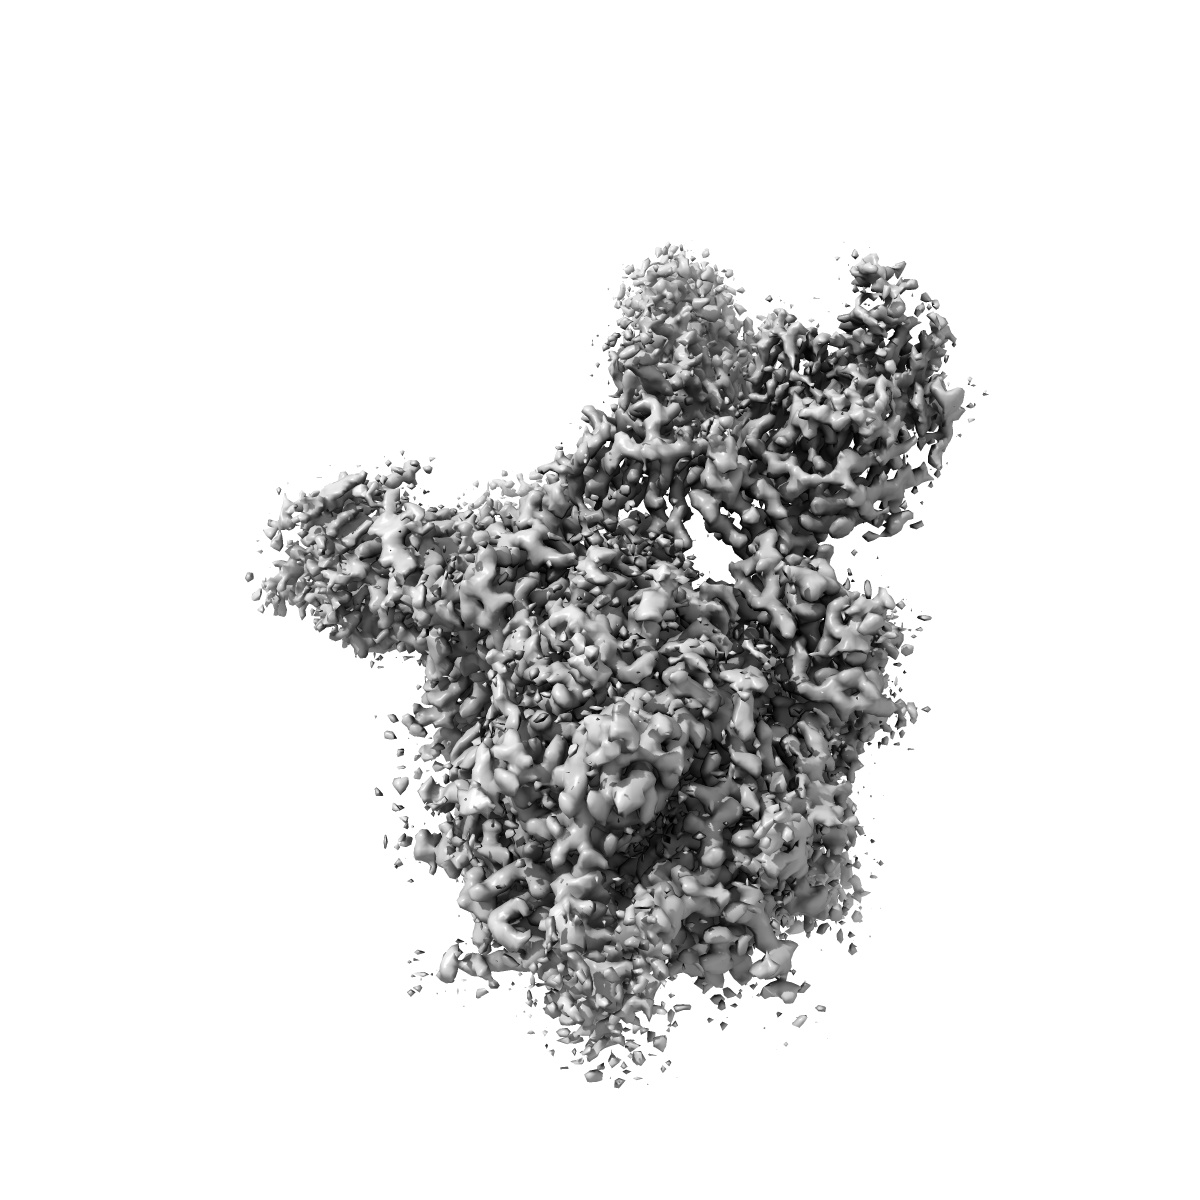

cryo EM map of the S protein of SARS-CoV-2 in complex bound with P2B-1A10

Single-particle2.8 Å

Sample: S protein of SARS-CoV-2 in complex bound with P2B-1A10

Fitted models: 7czq